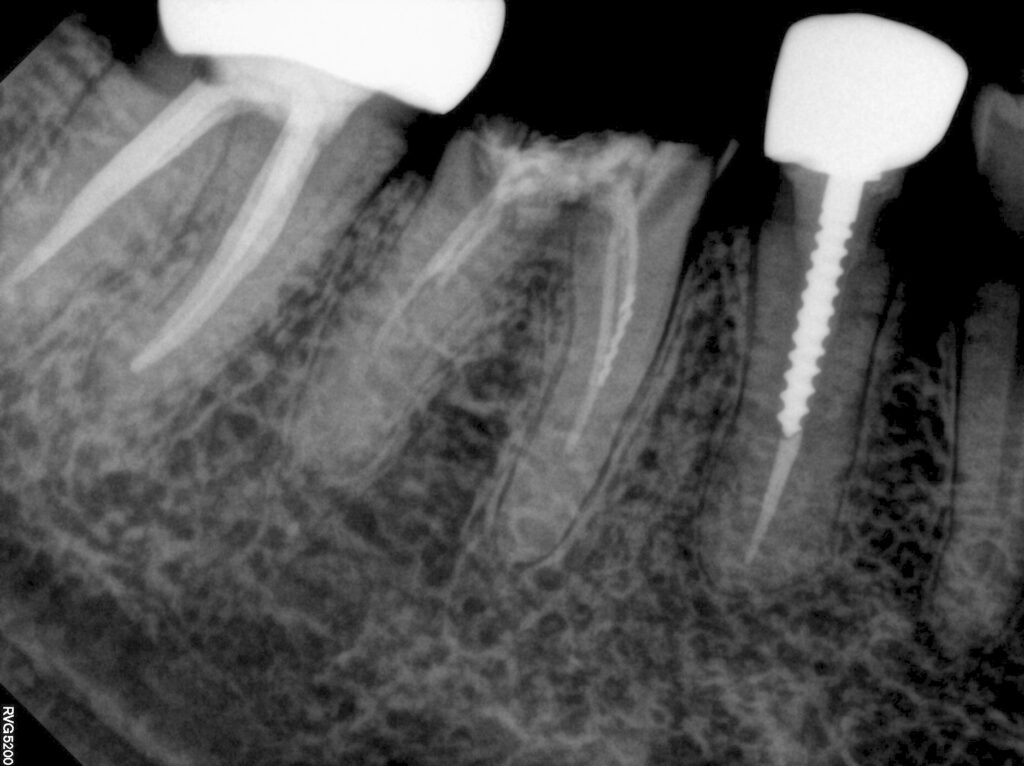

오히려 이런경우 치아 뿌리 끝 염증이 없고

더이상 근관을 뚫고 들어가기 어렵기 때문에

이쯤에서 근관 충전을 하기로 합니다

다행히 근관 하나 정도는

길이 확보가 되어서 끝까지 마무리할 수 있었어요

나머지는 되는데까지만 충전합니다